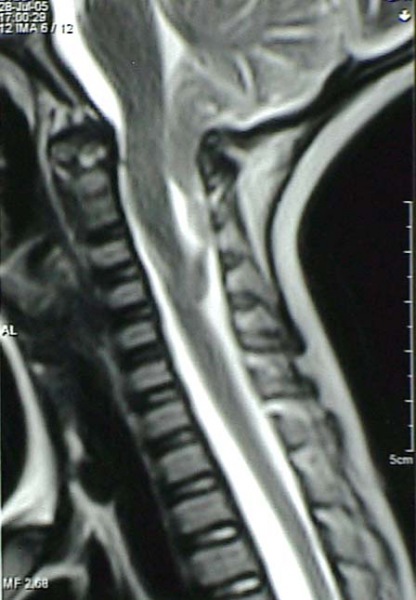

Аномалия Арнольда-Киари: MRI снимки